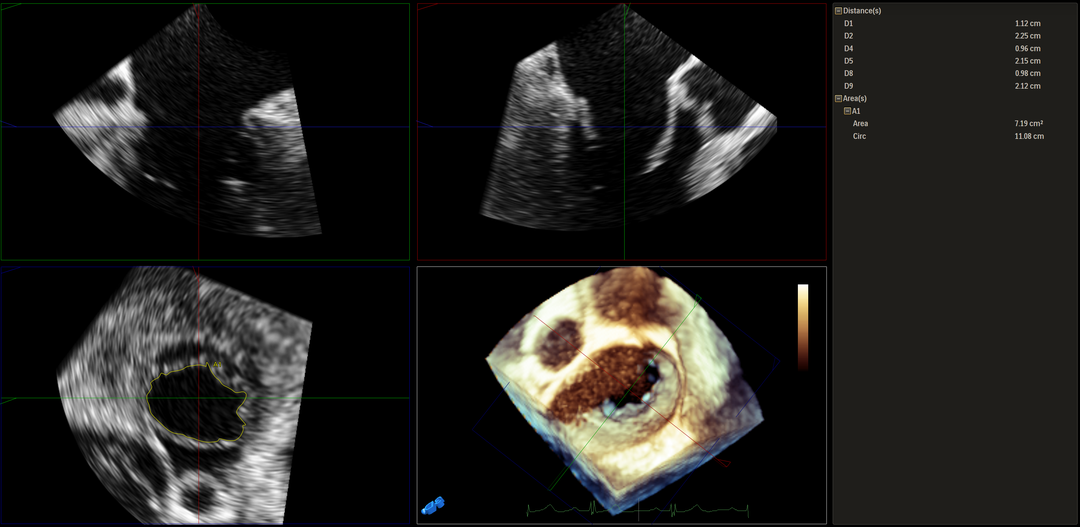

3D MV View:P2区脱垂

3D-color MV view:大量反流,起源于2区

Qlab软件勾画估测瓣口面积约:7.19cm²

二尖瓣口平均跨瓣压差:4mmHg

TEE Bicom view:二尖瓣后叶P2区大范围脱垂,部分累及1区及3区

Color-view:极大量反流,主要来源于2区